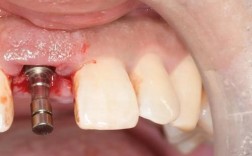

影像处理与结果解读

拍片完成后,技师会对图像进行处理(如调整对比度、三维重建),医生会结合临床检查和影像数据,分析牙槽骨条件、解剖结构风险,最终制定种植方案(如种植体型号、植入位置、是否需要植骨等),并向患者详细解释。